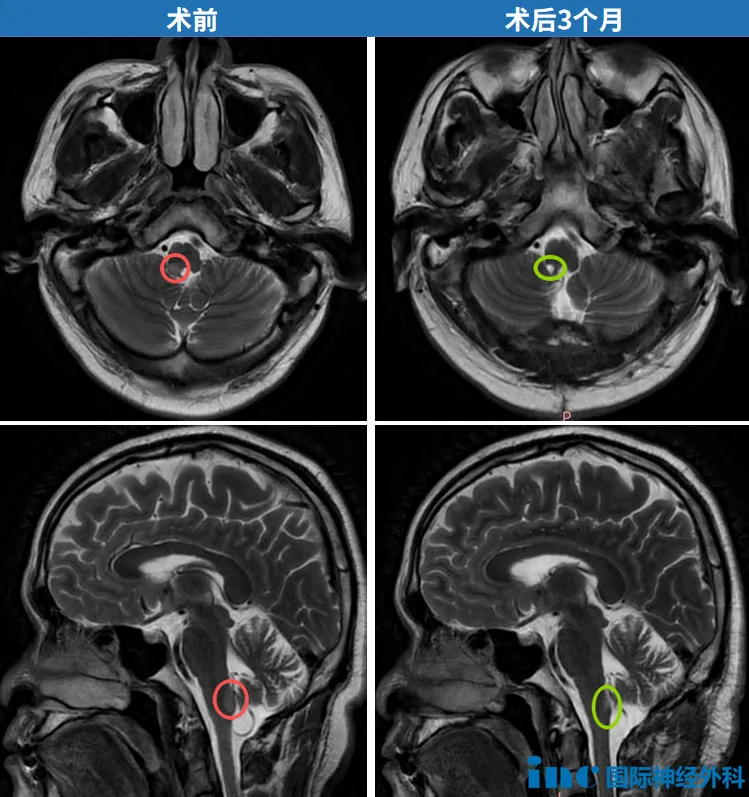

谁按下了快进键?让这个胶质瘤快速蔓延? 年过半百的李先生出现腿部发麻,腰痛,无法行走。经在当地医院检查后诊断为延髓肿瘤,医生认为这个位置手术风险太大,不建议手术。不到一个...

脑干延髓,位于大脑核心区,其内含有呼吸、心跳、意识觉醒、吞咽等基本生命活动中枢,是维持生命关键的神经结构,含有全部的神经传导通路。 历年来,包括延髓在内的整个脑干区域一直...